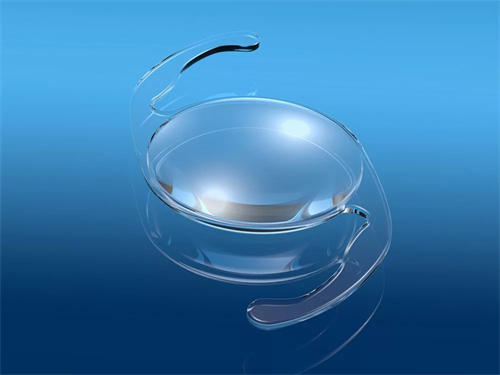

生物相容性优化:

晶体材料抗撕裂性提升,术后晶体移位风险降低,适合角膜条件复杂或瞳孔较大的患者。

材料科学进步:

采用疏水性丙烯酸酯材料,降低术后后发性白内障发生率。

手术操作便捷性:预装式设计缩短手术时间。